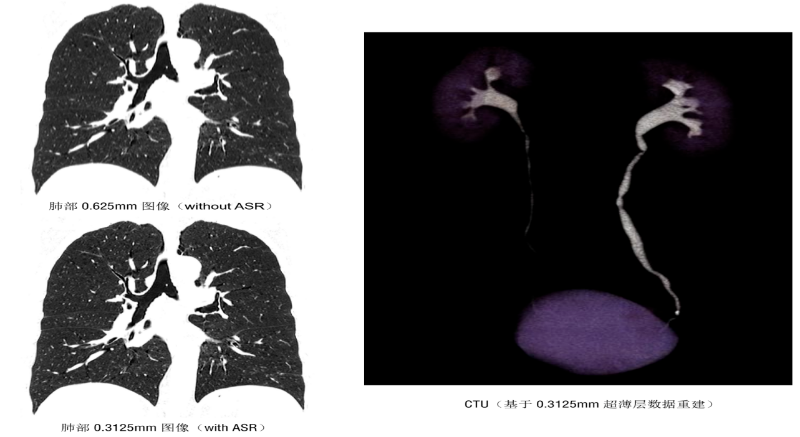

该设备集 “超高清成像、低剂量防护、极速扫描”于一体,将为辖区居民提供更精准、更安全、更便捷的诊断服务,标志着石岩人民医院在医学影像领域的诊疗水平迈入新阶段。 作为临床诊断的 “眼睛”,ANATOM X980的三大核心功能,直击患者就医痛点与临床诊断需求。 人性化设计与智能定位系统 ANATOM X980配备80厘米宽大机架孔径,结合舒缓氛围灯光,有效缓解患者检查时的紧张情绪。 设备搭载四块大尺寸高清触控屏,方便技师多角度掌握患者信息与设备状态,并可通过按键与无线遥控实现灵活摆位,大幅降低操作负荷,提升检查效率。 利用深度双目视觉认知系统,采用深度学习方式,赋予设备认知能力和行为,使系统能智能识别人体多个定位点,并在智能触屏终端上显示扫描部位,同时还能够自动识别拟扫描部位的等中心位置,实现精准化、智能化的患者摆位。 宽体探测器与极速扫描能力 依托16厘米宽体探测器结合0.25s的扫描速度,可实现全器官一站式扫描。 ▲ 心脏冠脉、主动脉、肺动脉联合扫描 通过AccuGating门控触发技术和 Adose mA电流调制技术和全新的算法、领先的AI成像技术手段,结合一键冠脉提取及分析、IVUS 模拟血管内超声、斑块分析、心功能分析、钙化积分分析、血管内窥镜、CT-FFR 技术,为患者带来了高成功率、高舒适度的单心跳(One-beat)心脏冠脉(CCTA)检查体验。 ▲ 心率103bpm 得益于一次单圈旋转最大16cm的覆盖范围,结合0.25s 的极快速度和安科独创的4D图像重建技术,在充分保证整个器官的各个位置数据的同时、同源、同向的条件下,实现了自由呼吸模式的肺部检查,为幼童、意识不清等患者肺部检查提供了最佳检查方式,为分析结果和治疗决策的准确性提供了保证。 高清影像与低剂量技术 ANATOM X980采用了基于深度学习技术的Artist 高保真图像降噪算法来对低剂量图像进行优化和处理。 与其他的算法相比,Artist 可以实现更彻底的噪声与图像信号分离,并确保在处理过程中图像细节信息不丢失,进而获得低剂量下高分辨的临床影像。 灌注扫描的剂量问题一直是临床中的老大难问题。ANATOM X980的超低mA采集及Artist还可在脑卒中解决方案中,可确保低剂量下获得精准的灌注数据。 此外,ANATOM X980还有其它几大独具特色的功能。 1.AI超分辨薄层重建技术(ASR) ANATOM X980搭载基于AI技术的高分辨率薄层图像重建技术(ASR=AI Super Resolution reconstruction),该技术利用神经网络处理单元通过深度学习的方式,对带有伪影的混叠投影数据进行伪影校正和重建,可显著降低混叠伪影,提高 CT 图像的分辨率,获得高分辨 0.3125mm 的超薄层图像,从而提高临床诊断准确性。 2.AccuImage 2048×2048显微成像 将图像数据量提高 16 倍,可显示和观察更多的病变影像细节。 3.AccuSpiral能谱成像 基于AI迭代重建与能谱解析技术,可定量分析组织成分,辅助肿瘤良恶性鉴别、结石成分分析及出血定位,为临床提供形态与功能融合的多维度信息。 目前,ANATOM X980 已在石岩人民医院影像科正式投入使用,从常规体检到复杂病症诊断,从成人检查到儿童诊疗,全方位满足临床需求。 石岩人民医院将以这台 “精准诊断利器” 为依托,持续提升诊疗能力,让居民在家门口即能享受到高质量医疗服务,用科技守护每一位居民的健康! 咨询电话 0755-27609000转0121 石岩人民医院放射科 石岩医院放射科现有医护42人,其中主任医师1名,副主任医师5名,中级职称24名,初级9名,助理技师、岗培各2名。 设备由数字化DR、CT、MR、DSA和骨密度仪等组成。中心设备齐全,拥有世界上先进的1.5T磁共振(MR)一台;螺旋CT3台(包括安科256排512层CT1台、安科64排128层CT1台、安科32排CT1台)。 数字减影血管造影机(DSA)1台;数字胃肠机1台;数字化DR和移动DR共6台;并配有现代化的PACS、HIS、肺结节和心脑血管AI辅助后处理诊断系统。 审核|梁雄 责编|马章林 审校|张永东 图文|郭文霞 编辑|冯丽萍 校对|吴曼莉